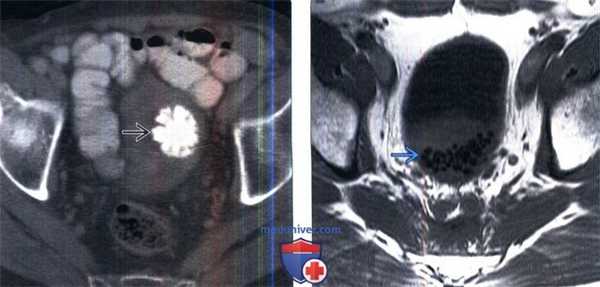

(Слева) КТ с контрастированием, аксиальный срез: типичная картина коралловидного камня мочевого пузыря, который обычно состоит из дигидроксида кальция. Они чаще формируются в мочевом пузыре, нежели чем в верхних мочевых путях.

(Справа) МРТ мочевого пузыря, Т1-ВИ, аксиальный срез: множественные округлые очаги исчезновения сигнала в нижней части просвета мочевого пузыря, представляющие собой камни у мужчины с заметным увеличением предстательной железы. Конкременты мочевого пузыря гипоинтенсивны на Т1В и Т2В изображениях, вследствие диамагнитных свойств солей кальция.